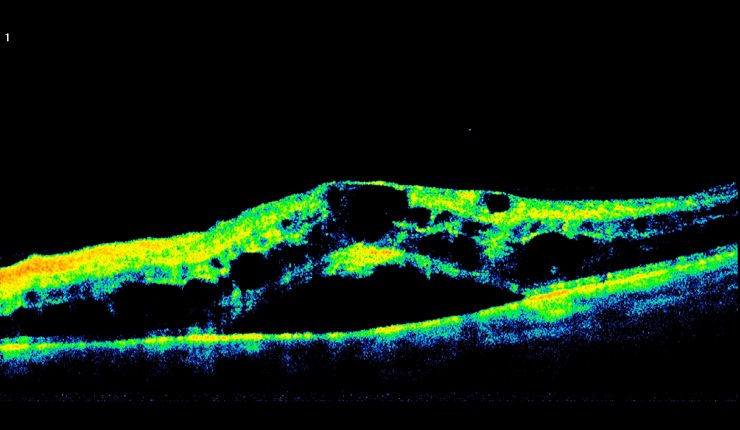

3D OCT of retinal angiomatous proliferation (RAP) showing news vessels tracking through the retina and associated intra-retinal oedema.